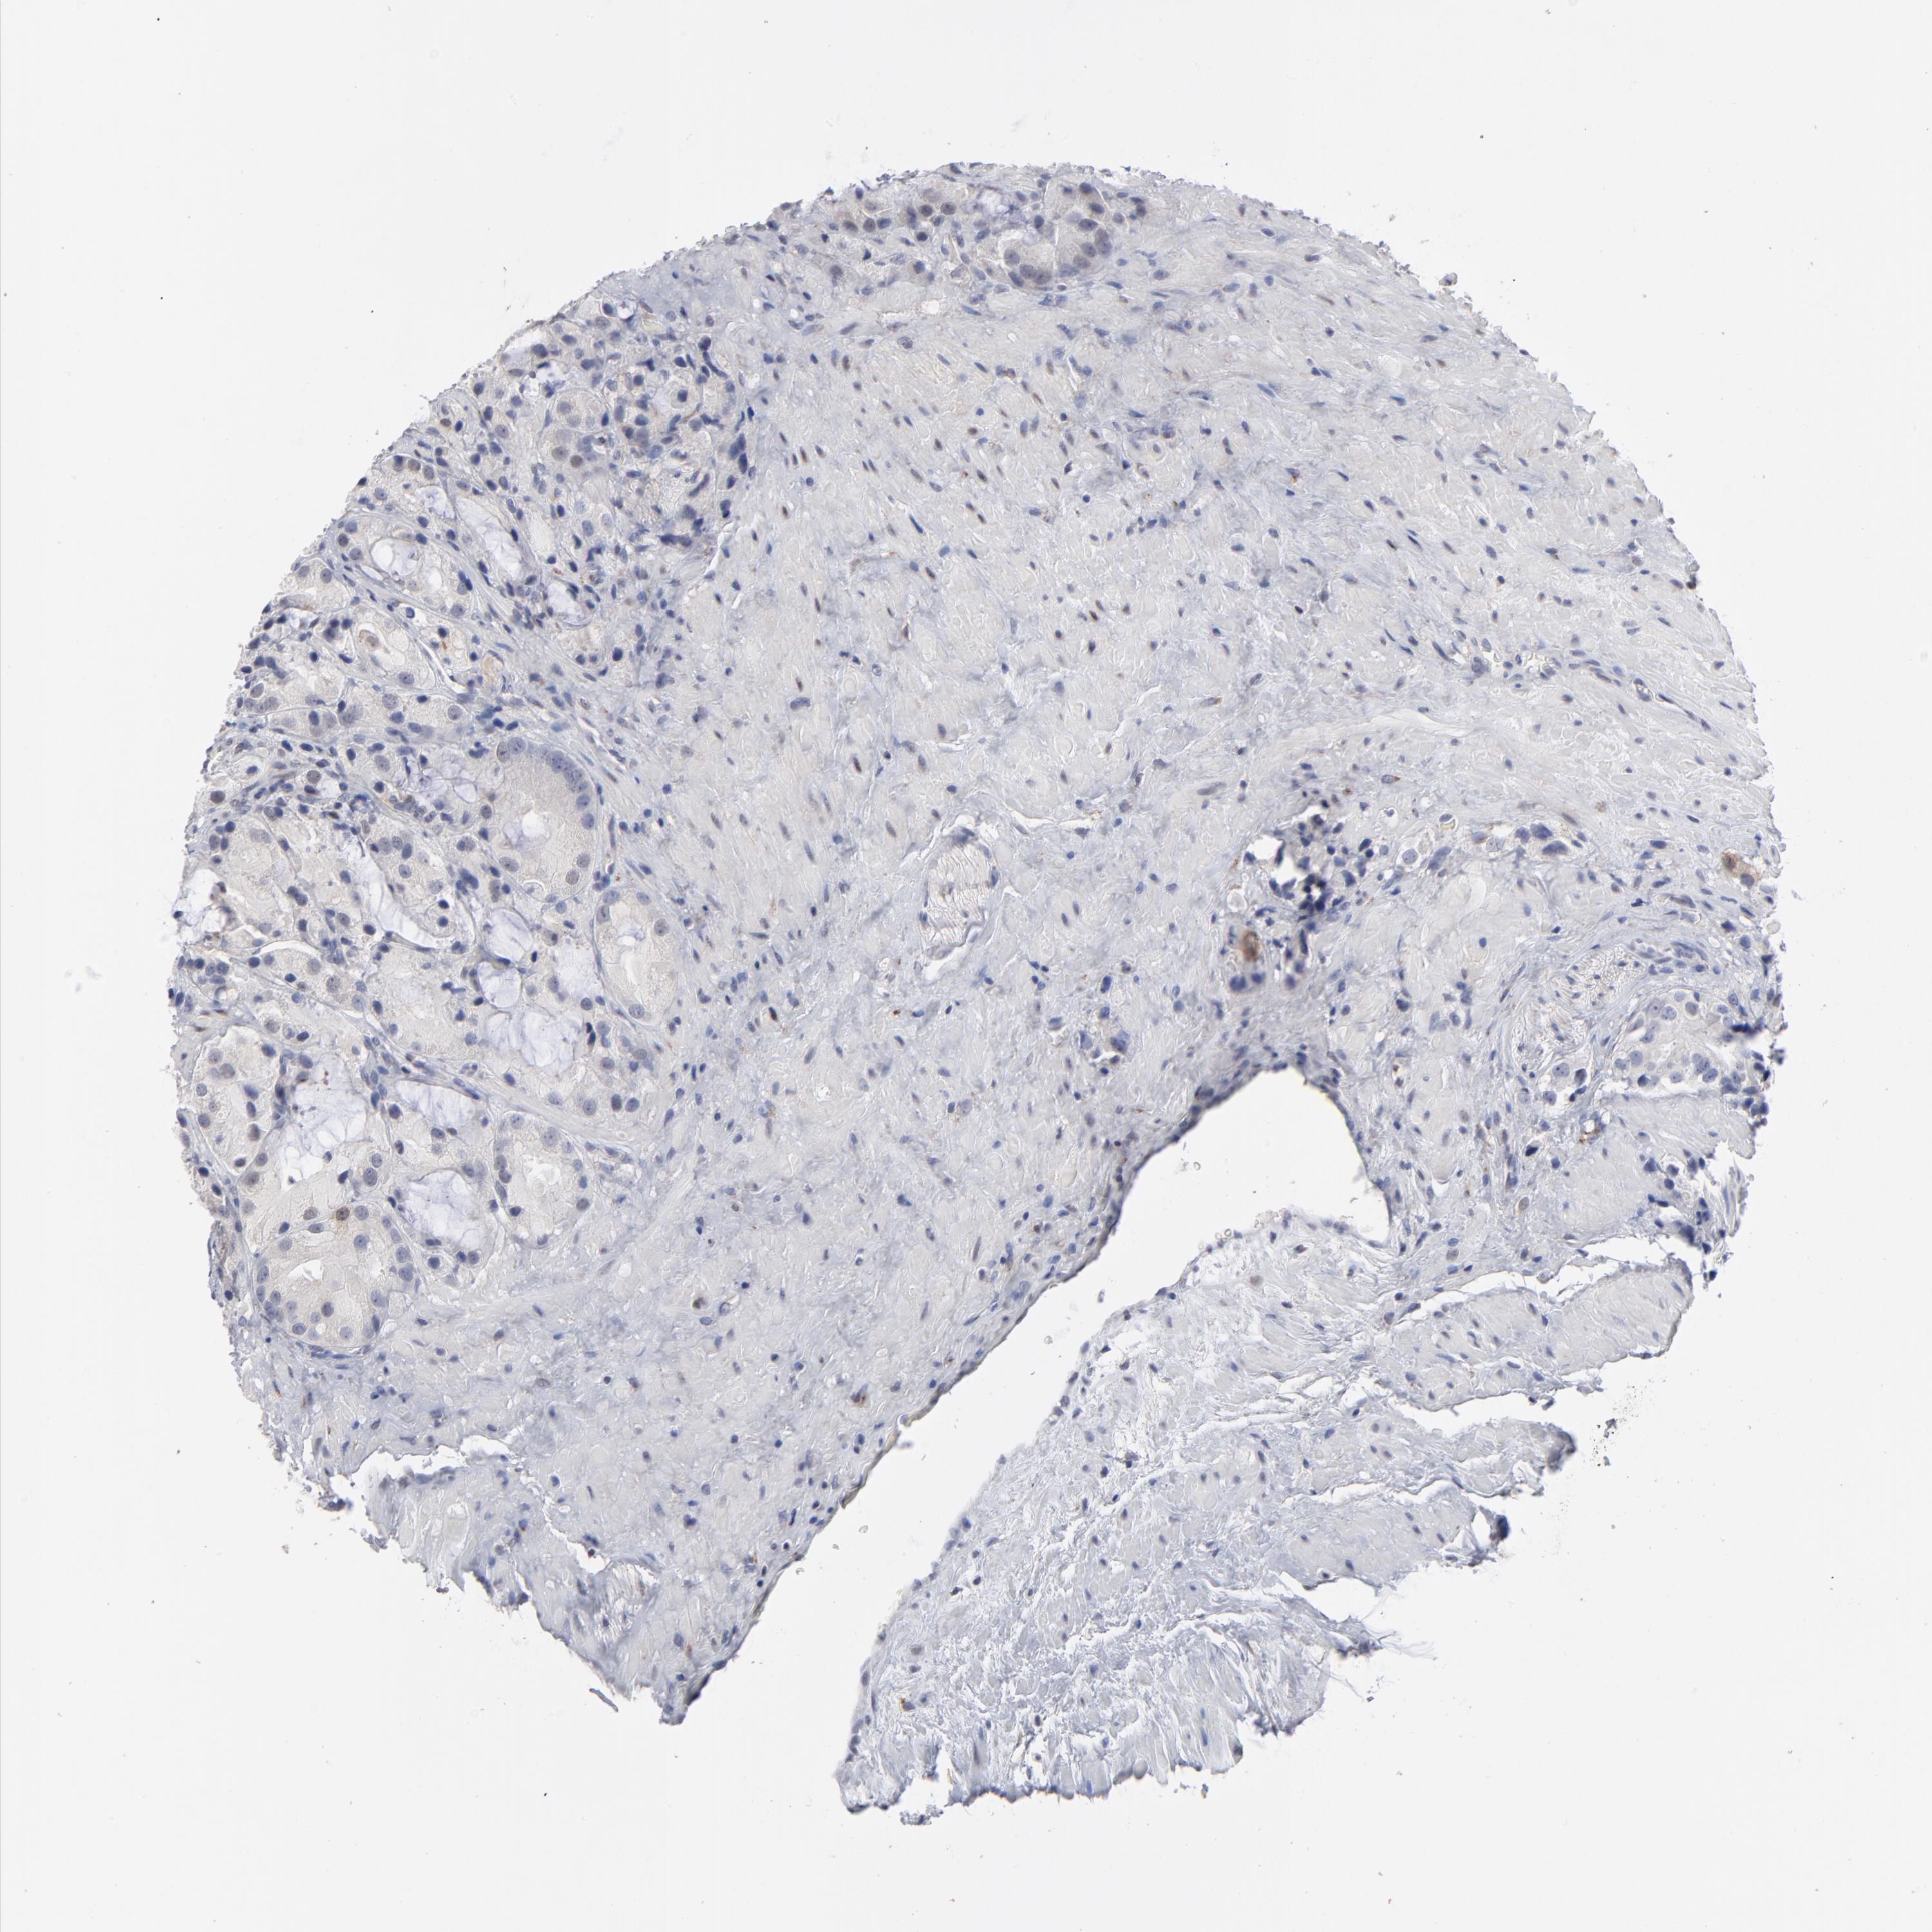

PROSTATE CANCER - Protein expressioni

A mouse-over function shows sample information and annotation data. Click on an image to view it in a full screen mode. Samples can be filtered based on level of antibody staining by selecting one or several of the following categories: high, medium, low and not detected. The assay and annotation is described here.

Note that samples used for immunohistochemistry by the Human Protein Atlas do not correspond to samples in the TCGA dataset.

Antibody stainingi

Antibody staining in the annotated cell types in the current human tissue is reported as not detected, low, medium, or high, based on conventional immunohistochemistry profiling in selected tissues. This score is based on the combination of the staining intensity and fraction of stained cells.

Each image is clickable and will lead to virtual microscopy that enables deeper exploration of all samples and also displays staining intensity scores, fraction scores and subcellular localization as well as patient and tissue information for each sample.

Antibody HPA002636

Antibody CAB001454

Staining

High

Medium

Low

Not detected

Intensity

Strong

Moderate

Weak

Negative

Quantity

>75%

75%-25%

<25%

None

Location

Nuclear

Cytoplasmic/membranous

Cytoplasmic/membranous,nuclear

Adenocarcinoma, Low grade

Adenocarcinoma, Medium grade

Adenocarcinoma, High grade